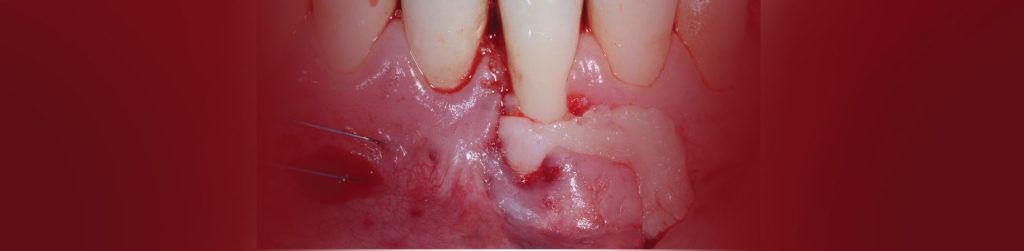

בסמוך למרפאתנו הקמנו חדר הרצאות חדשני וייחודי. ייעודו של האגף החדש הינו להגשים חלום יקר לליבנו, לממש ולקיים מרכז להכשרה קלינית לרופאים ובהדרכה אישית: A PRIVATE ACADEMY. במרכז יתקיימו הרצאות, קורסים עיוניים ומעשיים בהם תהיה צפייה בניתוחים בשידור חי, מחדר הניתוח בזכות מיטב הטכנולוגיה החדשנית. במתחם החדש, אנו נארגן מגוון רב של פעילויות, ומאמינים כי ביכולתנו לתרום מניסיוננו לטובת ציבור רופאי השיניים הכלליים. הקורסים מיועדים לכלל ציבור רופאי השיניים המעוניינים להעשיר את בסיס הידע ואת יכולתם הקלינית בתחומים שונים (פריודונטיה, אימפלנטולוגיה ואסתטיקה), דבר שישרת אותם במרפאתם. המרצים יהיו רופאי המרפאה יחד עם רופאים בכירים ומומחים נוספים אשר יצטרפו לצוות.